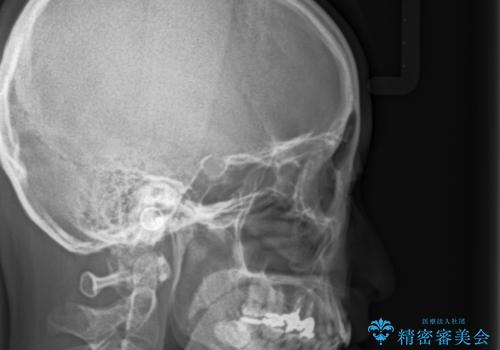

- 前歯の歯並びが気になることを主訴に来院された患者様です。

顎が小さく歯を並べるためのスペースが足りないため、

上下の前歯の歯と歯の間をすく処置(ディスキング)を行いました。

矯正装置:インビザラインフル (初回13stage+リファインメント11stage:計1年)